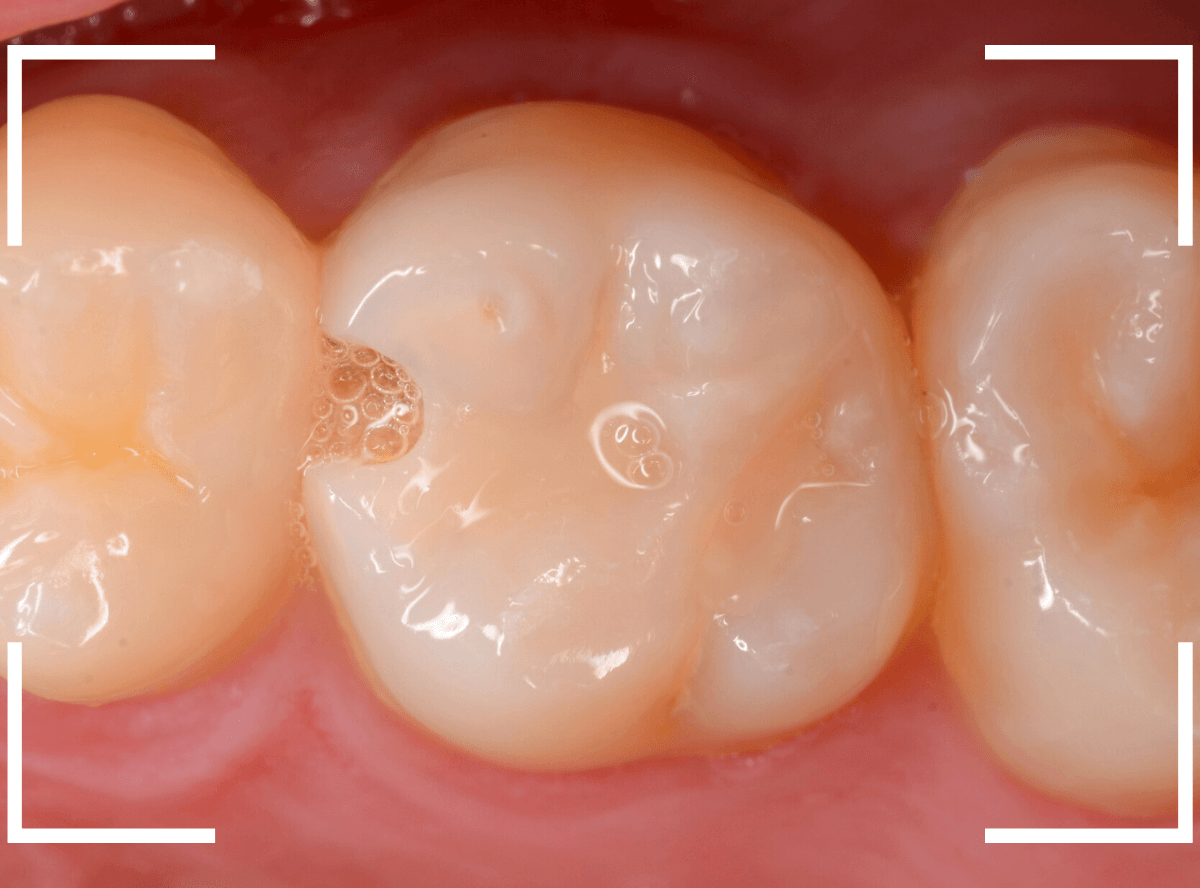

Case.4 2年間メンテナンスを中断している間に、深く虫歯が進行!

定期メンテナンスを2年間中断後に、来院された患者さんです。

見た目は手前の歯との間の小さな虫歯に見えますが、

「普段は痛くない」

「食事の時に物がつまる」

「物がつまった時に噛むと痛い」

・・・と、自覚症状は乏しいが、実際は大きな虫歯の場合の症状あるあるの訴えでした。

レントゲン写真で虫歯の状況を確認します。

赤い線が虫歯の部分、青い線が歯の神経の部分です。

思った通り、入り口の小さなすき間の中は、神経まで達してしまいそうな大きな虫歯になっていました。

しばらく経過観察後、幸運にも特に症状なく経過しましたので、型どりをして、つめもの(メタル・インレー)で修復する事ができました。